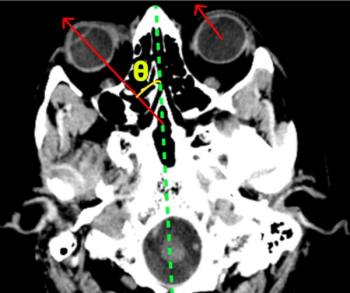

Artificial intelligence (AI) accurately diagnosed 79 percent of proximal large vessel occlusions with an ipsiversive gaze deviation on non-contrast computed tomography (CT), according to new research findings presented recently at the Society of Neurointerventional Surgery’s (SNIS) 19th Annual Meeting in Toronto.